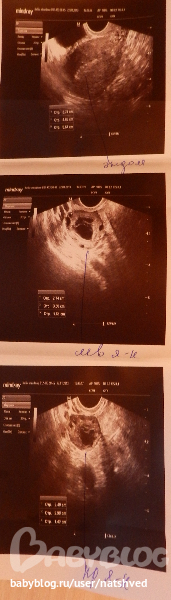

сегодня сходила на УЗИ

и вот что - 2ЖТ в каждом яичнике по одному 17мм и 15мм

но Г сказала, что возможно это кисты, так как рано для О